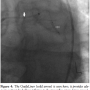

coming off of the LM at a very acute angle, which was felt to be a risk for future stenosis of the LAD. The LM was deemed not to be inter-arterial (running between the aorta and pulmonary artery). During the current admission, cardiac catheterization revealed that both vein grafts were totally occluded. RCA was totally occluded, with filling of the RPDA via collaterals from the left. Additionally, there was a critical 99% stenosis in the proximal LCX (Figure 1). The patient was referred for re-operation CABG. However, the surgeons only considered him a candidate for re-operation if the LM was coursing inter-arterially. Upon repeat cardiac catheterization and by placing a catheter in the pulmonary artery, it was confirmed that the LM actually coursed posterior to the aorta, and not inter-arterially (Figure 2). The LM had an intra-septal course and it gave off large septal branches before bifurcating; however, there was no systolic compression of the LM.

When the LM originates from the right sinus of Valsalva, it may be classified into one of four types: a) the LM passes between the aorta and pulmonary trunk, posteriorly and adjacent to the pulmonary trunk; b) the LM passes anteriorly over the right ventricular outflow tract; c) the LM courses along the crista supraventricularis intramyocardially or subendocardially, surfacing in the proximal interventricular sulcus; and d) the LM may rise to the right of the RCA and pass posteriorly to the aortic root or anterior to the pulmonary trunk.1 In our patient, the LM coursed posterior to the aorta (Figure 2).